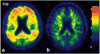

A central issue in cognitive neuroscience of aging research is pinpointing precise neural mechanisms that determine cognitive outcome in late adulthood as well as identifying early markers of less successful cognitive aging. One promising biomarker is beta amyloid (Abeta) deposition. Several new radiotracers have been developed that bind to fibrillar Abeta providing sensitive estimates of amyloid deposition in various brain regions. Abeta imaging has been primarily used to study patients with Alzheimer's Disease (AD) and individuals with Mild Cognitive Impairment (MCI); however, there is now building data on Abeta deposition in healthy controls that suggest at least 20% and perhaps as much as a third of healthy older adults show significant deposition. Considerable evidence suggests amyloid deposition precedes declines in cognition and may be the initiator in a cascade of events that indirectly leads to age-related cognitive decline. We review studies of Abeta deposition imaging in AD, MCI, and normal adults, its cognitive consequences, and the role of genetic risk and cognitive reserve.